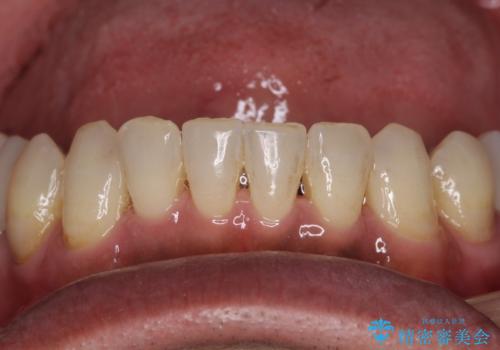

全体的に中等度の歯周病と診断されたため、歯周外科処置やインプラントによる咬合回復から進めて行き、矯正治療による歯列改善を行った後にオールセラミッククラウンにて補綴することとしました。

歯槽骨の再生治療を行ったため、外科処置後の静置期間がながくなり、4年弱の治療期間となりました。

初診来院時には矯正治療を行うことは想像していなかったようで、治療後には咬みやすさだけでなく、前歯が大変審美的に仕上がり、患者様には大変満足していただきました。